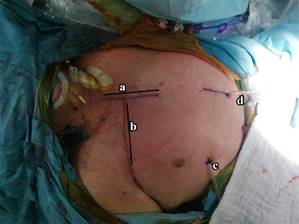

Carrying out dissection by planes, the pectoralis major is located. With blunt dissection, the pectoralis minor is located on its medial border, which is retracted laterally without the need to section. Intercostal muscles are dissected on the upper edge of the third rib, by placing an automatic Finochietto retractor (Figure 3).

Figure 4: Wide exposure of vertebral bodies. a) Patient’s chin. b) Right lung parenchyma retracted inferiorly. c) Malleable retractor protecting mediastinal structures. d) Malleable retractor protecting lung parenchyma. White circle indicates corpectomy area and placement of expandable cylinder.